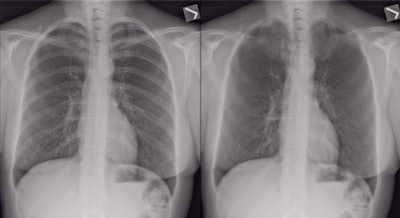

Left, chest radiograph; right, bone suppression. Image courtesy of Dr. Yun Wang.

Left, chest radiograph; right, bone suppression. Image courtesy of Dr. Yun Wang.In their observer study, the researchers included 95 standard, posteroanterior digital chest radiographs from patients with a solitary nodule confirmed by CT and 46 control subjects. Four observers -- two radiologists and two residents -- indicated their confidence level regarding the presence of a nodule for each lung on a scale of 1 to 5, with 1 being not suspicious and 5 being definitely suspicious.